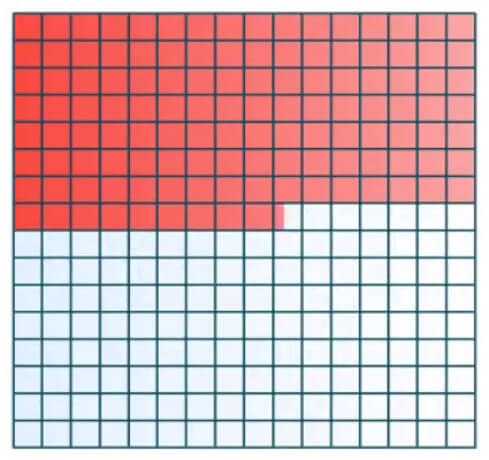

The space of Fourier is divided into 4 symmetrical parts, 2 by 2.The K space is symmetrical according to a complex conjugated symmetry around the center. This property is used for rapid sequences for which we fill in only half the Fourier space and the other half is mathematically deduced. This is the case for single-shot fast spin echoes known as SSFSE or Haste sequences. Haste stands for “half acquisition spin turbo echo.

Filling the K Space

In most sequences, the Fourier space is filled in line by line: this is called linear filling. For other sequences, space is also filled in line by line but starting at the center: this is the centric mode. GE and Siemens scanners use this. Or Linear Low-High as it is called on Philips. This filling can also be done starting in the center but in a centrifugal manner or snail-shaped. This is centric elliptical mode common on GE or Siemens scanners or central as referred to on Philips.

The time of an acquisition is the time required to fill the Fourier space, multiplied by the number of times we want to fill the space. To start, we take a sequence which is filled linearly. The time needed to fill a Fourier space is the time to fill in one line multiplied by the number of lines.

In reality, the space of one TR is needed to fill one line and we have as many lines as indicated by the phase matrix. Another parameter involved is the ETL or echo train length or turbo factor as it is sometimes called. It is the number of lines of the Fourier space filled in at each TR. The number of Nex is the number of times the Fourier space will be filled. A good analogy for the number of Nex’s is a painter repainting a wall: the more coats of paint, the better the result but more time is required to fully paint the wall.